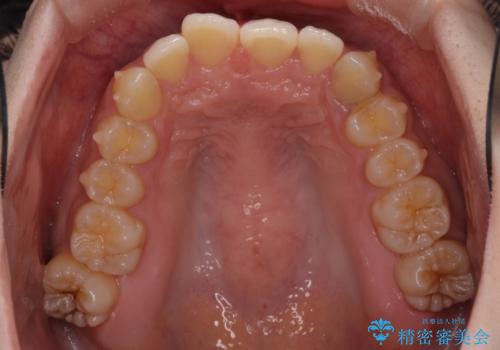

奥歯の倒れた歯を改善 インビザラインでの矯正治療

- 前歯のデコボコと奥歯の不正咬合を気にして来院された患者様です。

左右の大臼歯が全て鋏状咬合(シザーズバイト)になっており、治療が難航することが予想されましたが、インビザラインにより治療を行うこととしました。

最難関と思われたシザーズバイトは比較的短期間で解消されました。

しかし、治療中に2度の出産を経験され、治療期間は長くなってしまいましたが、咬みやすく、清掃しやすい歯列を獲得することができました。